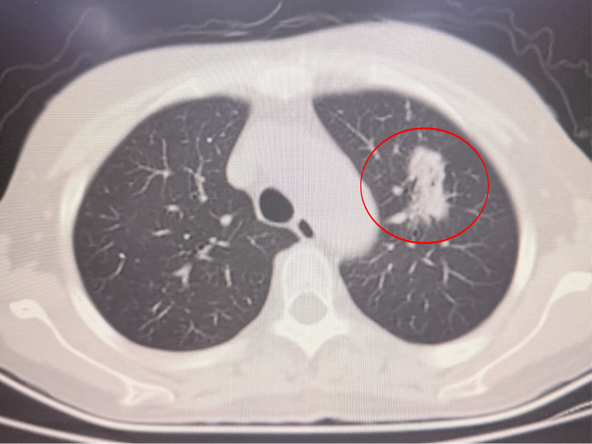

53岁的李女士常年受肾功能衰竭困扰,需依靠每日4小时血液透析维系生命。在她苦等匹配肾源、即将迎来肾移植曙光之际,术前PET-CT检查发现其左肺上叶靠近肺门处存在一枚直径1.3cm的混杂性磨玻璃样高危肺结节。

消融前影像

本次手术核心难点在于消融操作。患者病灶紧邻肺门,周围血管密集,且患者凝血能力欠佳,穿刺出血风险极高。在静吸复合麻醉的平稳支持下,陶冀教授团队通过精准影像定位实施分段穿刺,成功将消融针精准送达病灶核心。随后,团队以40W启动消融,根据情况实时调至50W,在9分钟的消融过程中精准把控范围,既确保覆盖病灶,又与肺门血管保持安全距离。术中患者心率、血压平稳,术后影像显示病灶已彻底消融,且无出血、气胸等并发症发生。

消融术中影像 消融术后影像